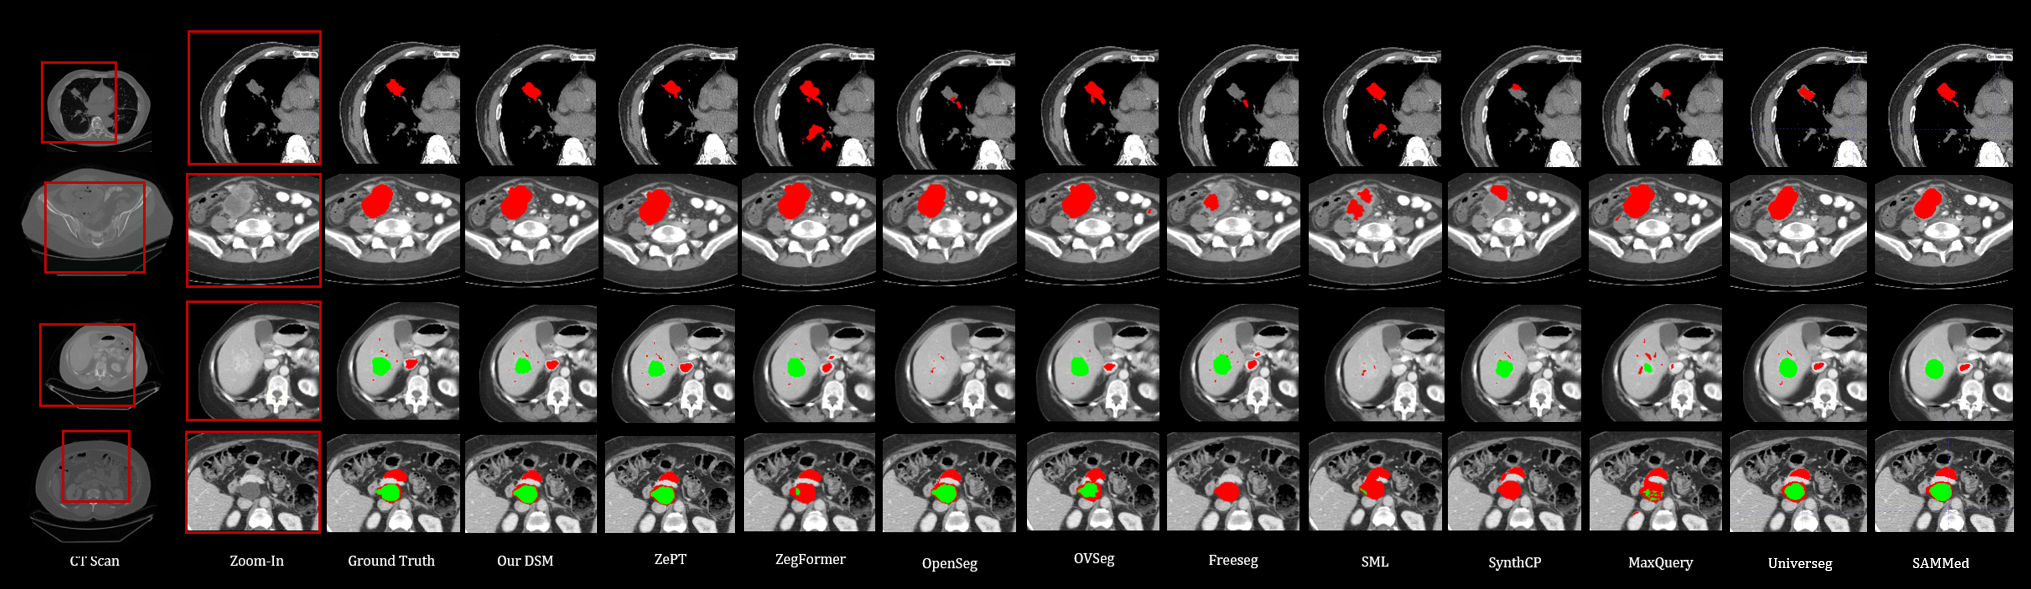

Figure 5 visualizes segmentation results on the MSD dataset from DSM and those baseline methods, where DSM demonstrates the best segmentation performance.

Figure 5 shows the qualitative results on DSM with medical segmentation models and highlights the advantages of DSM. Most competing methods suffer from incomplete segmentation of the target and misclassification of background regions as tumors (false positives). In contrast, DSM produces sharper boundaries and generates results that are more consistent with the ground truth than all other models.